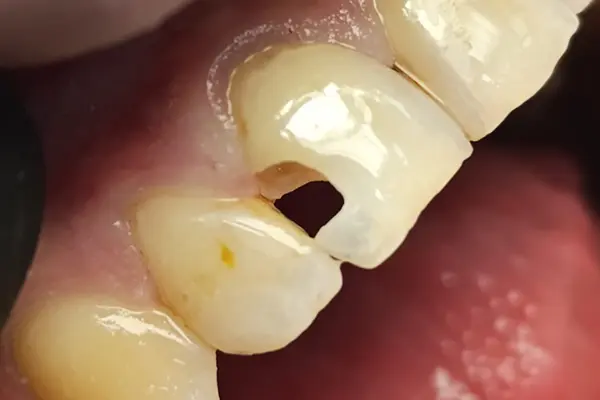

Этап 2

- Адаптивный слой из B&E flow.

- "Дентинное ядро" из Xs-Fil AO3.

- Эмаль Xs-Fil A2.

- Полировка.